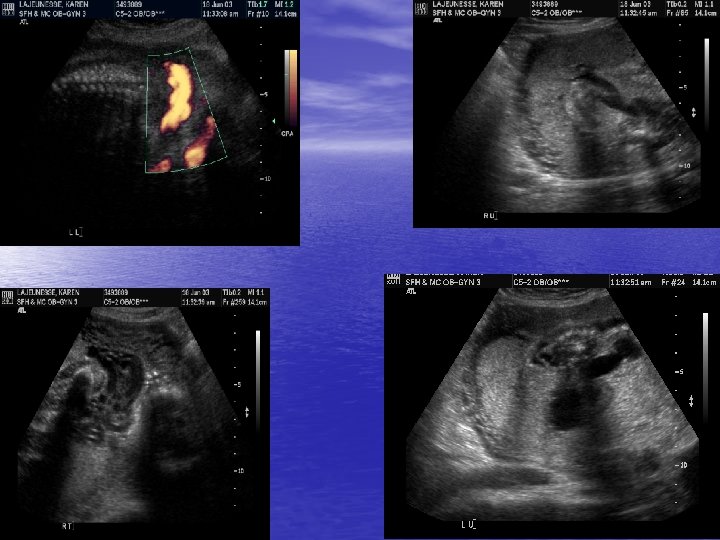

MFM Evaluation began • 6/18/03 – formal ultrasound revealed – Distended, thick walled bladder with a keyhole appearance in the area of the posterior urethra – Ureters and renal calyces were distended – Hydronephrosis – Left renal pelvis = 7 mm Right renal pelvis = 10 mm -- Amnioinfusion with 300 cc of warm normal saline was performed with asp. of 20 cc for chromosomal analysis

Classic “Keyhole” Sign

Thickened bladder wall

Distended Bladder

Dilated Rt and Lf Ureters

Dilated Right Kidney